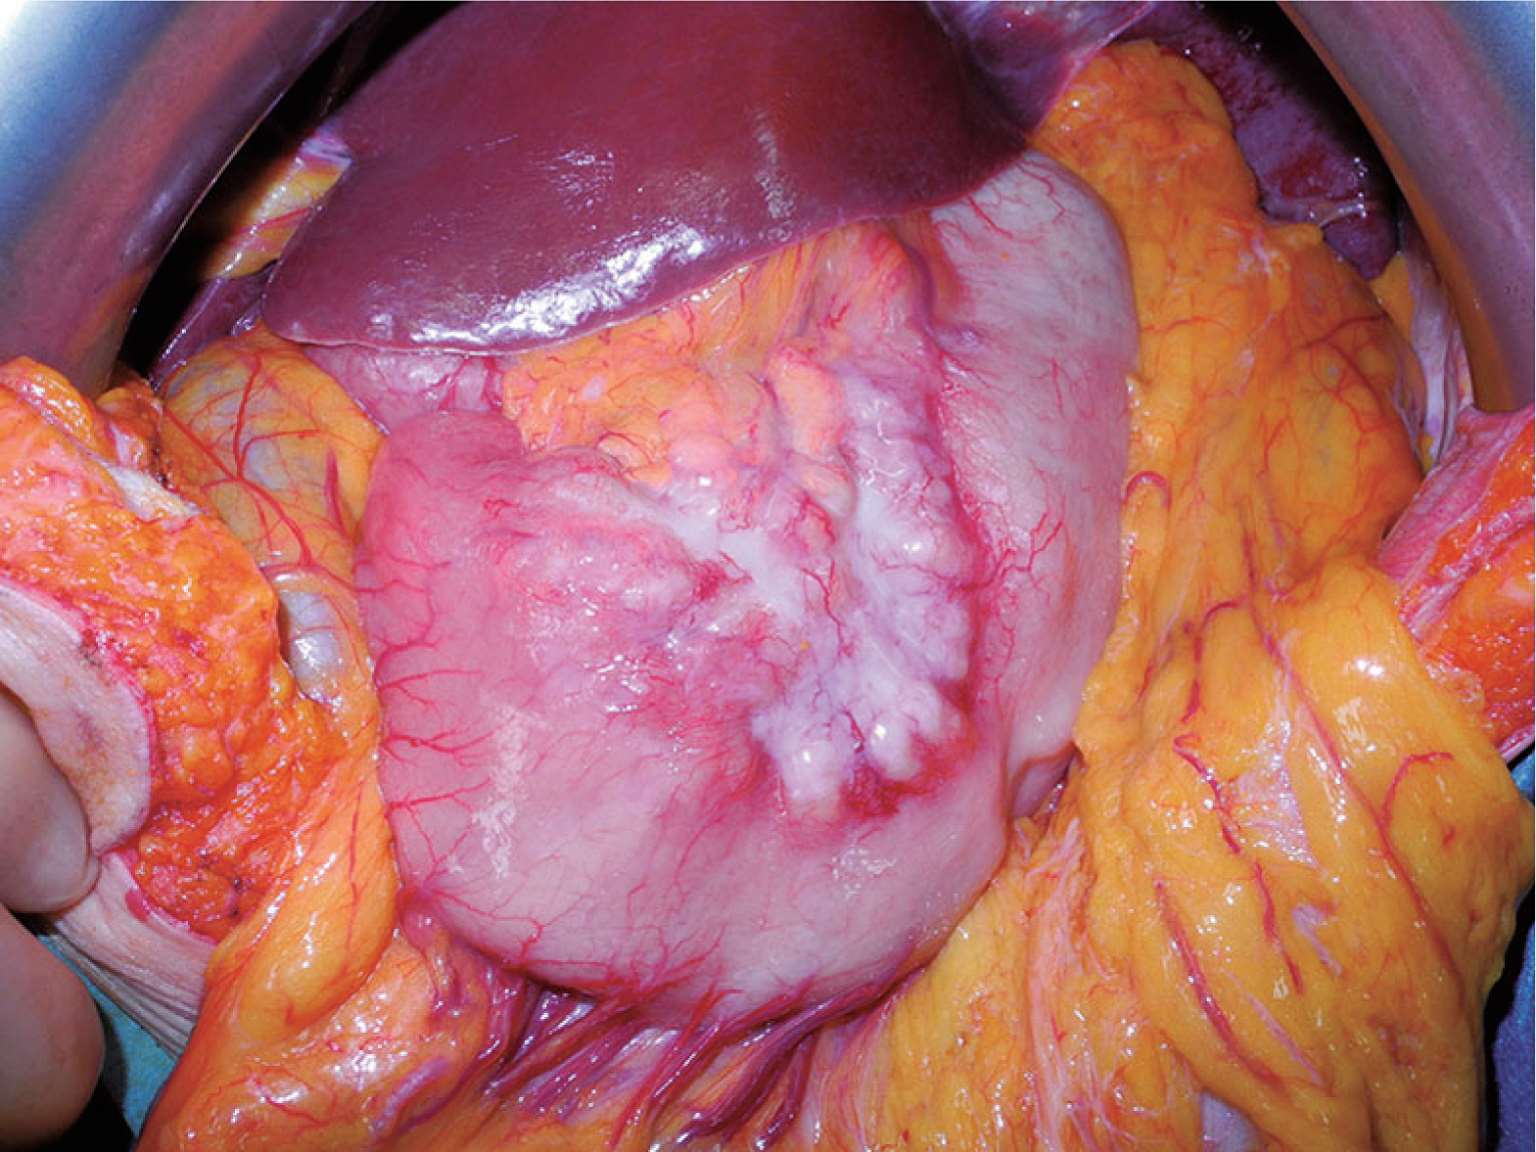

图2-8 弥漫浸润性胃癌是指胃癌细胞沿胃壁弥漫性浸润全胃,导致胃壁增厚,质地变硬,也称为“皮革样胃”。

图2-9 由于“皮革样胃”术前胃镜活检诊断困难,术中可行全层胃壁活检,以明确诊断。